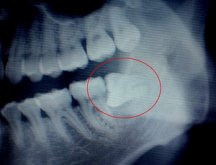

拔智齿对于每个人来说,可谓是又痛又恨,智齿在口腔内部潜伏的时候,不会对人体健康造成太大影响,然而智齿一旦发作起来,可会...【详情】